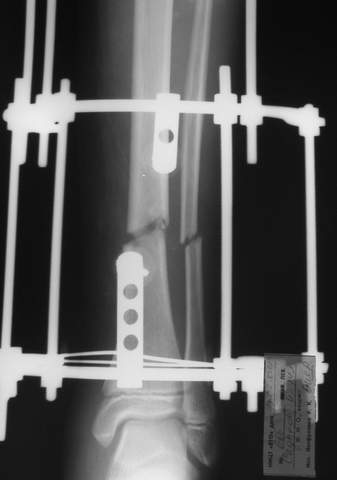

В аттачтах №№ 1 и 2 - примеры, когда 2 кольца не позволили послеоперационно

исправить смещение фрагментов большеберцовой (по ширине и вальгусное).

А казалось бы (#2) - поиграй на штангах и все влетит.

2

3a